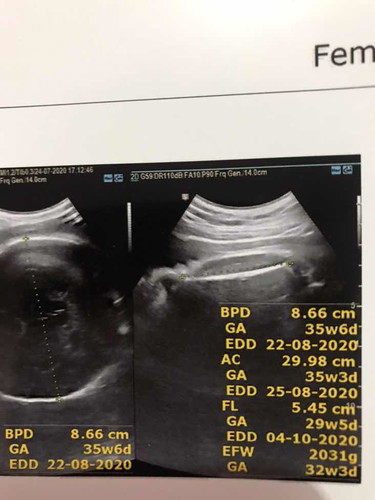

ตอนนี้34wหมอนัดผ่าคลอด 24 สิงหา น้ำหนักลูกน้อยเกินไปหรือป่าวค่ะ 2031 g เเม่ๆท่านอื่นลุกน้ำหนักเท่าไหร่

* ดูจากในแอพนี้ก็ใกล้เคียงน้ำหนักตามเกณฑ์นะคะแม่ 2,100กรัมค่ะ

ซาวตอน 34w 2200g ค่ะ กำหนด 28 สิงหา นัดผ่า 17 สิงหาค่ะ 🥰